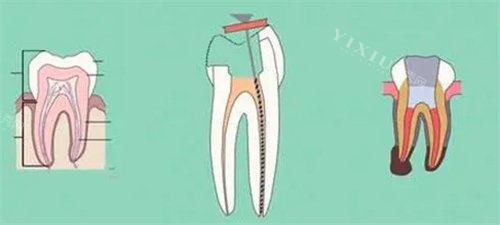

诊疗项目齐全,技术比较靠前:科室年门诊量达12万余人次,开设口腔内科、口腔修复科、口腔正畸科3个亚专科,并配备住院病房。广泛开展显微根管技术、智能化种植技术、隐形正畸技术、牙周及种植体周围软组织美学处理等特色技术,乃至口腔颌面部肉瘤、骨折等复杂手术。

设备靠前比较准,维持疗效:科室拥有口腔锥形束CT(CBCT)、根管显微镜、3shape口腔扫描系统等现代化设备,为比较准诊断和较高的效率治疗提供了强大支撑。